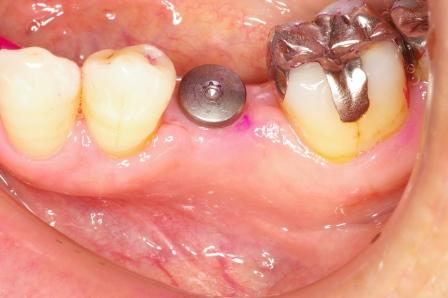

インプラント(人工の歯根)を入れた症例です。

歯の根っこにひびが入り、抜歯となった左下にインプラント(人工の歯根)を使って歯を入れました

前後の歯を削らずにすみます